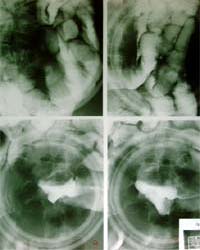

6.経口小腸造影 & 経口小腸二重造影 最初にバリウムを飲んで頂きます。透視台の上で体位を変えながら、バリウムを小腸と大腸の吻合部まですすめます。体位は、頻繁に変えません。流れを見ながら時間をおいて(10分〜20分)仰向けや横向きになって頂きます。この間に、おなかを押さえたりして小腸の狭窄や病変がないか見ていきます。大腸まで到達したら、発泡剤を飲んでもらって小腸をふくらまし全体の写真を撮っていきます。この検査にかかる時間は個人差があります。流れの速い患者さまは30分〜1時間、遅い患者さまは2時間〜3時間かかる場合があります。 |